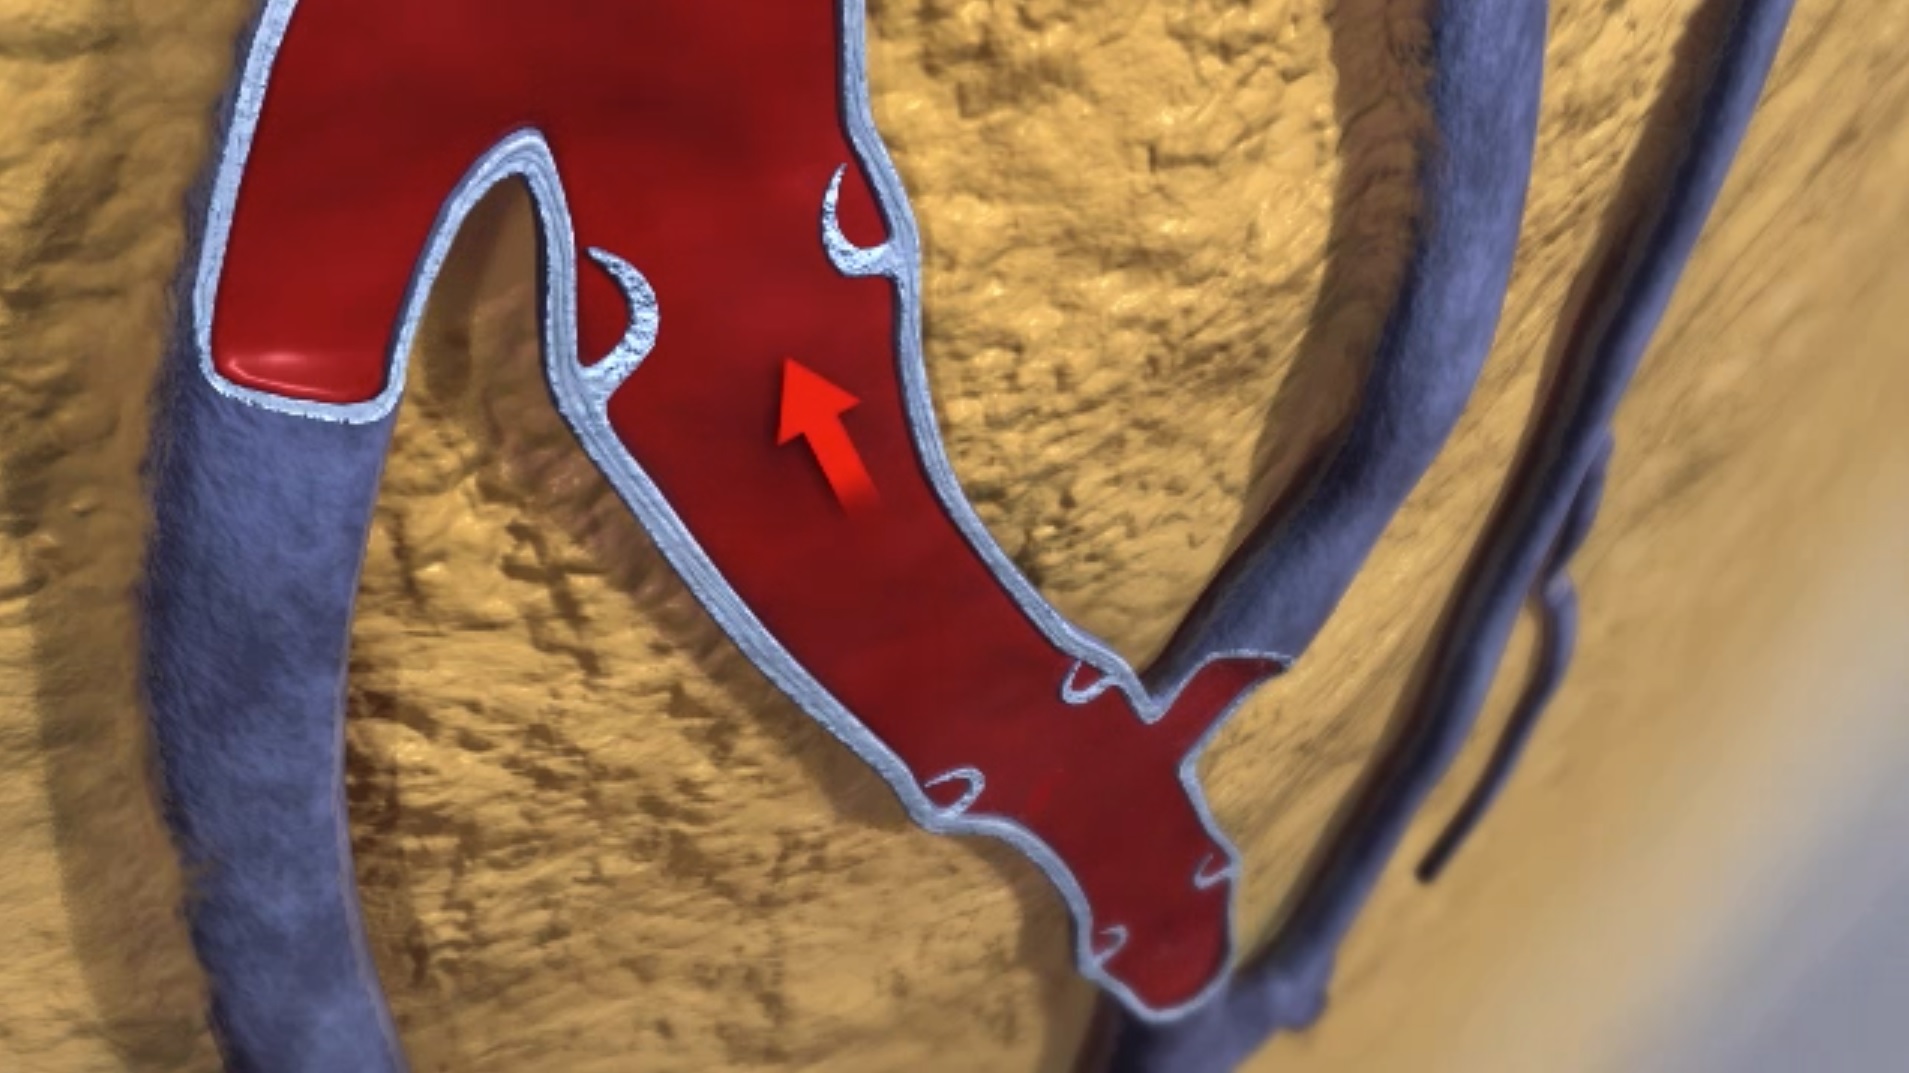

Srce pumpa krv preko arterija da bi isporučilo kiseonik i hranljive materije. Krv se vraća u srce kroz vene, kako bi se više krvi upumpalo u pluća da bi se „prikupilo“ više kiseonika. Krv u venama na nogama ide protiv gravitacije da bi se vratila u srce.

Krvni pritisak u venama je nizak, tako da u zidovima vena postoje ventili koji sprečavaju da krv teče unazad. Kada se mišići nogu grče, oni zapravo pomažu venama da krv dovedu do srca.

Neki ljudi imaju rastegljivije zidove vena, što usled jačeg pritiska dovodi do njihovog proširenja. Krv u ovim venama se teško vraća u srce, a pritisak odozgo usled sile gravitacije na stub krvi „primorava“ tanke zidove vena da se prošire prema spolja, čineći ih tako većim, proširenim. Proširena vena sadrži više krvi, a to takođe vrši pritisak na pomenute ventile u venama koji sprečavaju da se krv vraća. Takav pritisak u proširenim venama utiče i na otežan rad ventila.